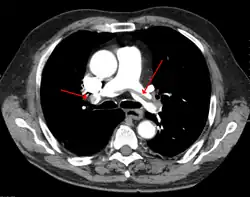

Lungeemboli eller blodprop i lungerne er en komplikation ved dyb venetrombose. Trombosen (blodproppen) løsner sig og følger blodstrømmen i venen til hjertet og derfra ud i lungekredsløbet. Her sætter den sig fast og blokerer blodtilførslen til en del af lungen. En blodprop kan løsnes når som helst, men ofte i forbindelse med aktivitet.

Diagnosen kan fastslås ved lungeskintigrafi med lungeperfusionsskintigrafi og lungeventilationsskintigrafi.